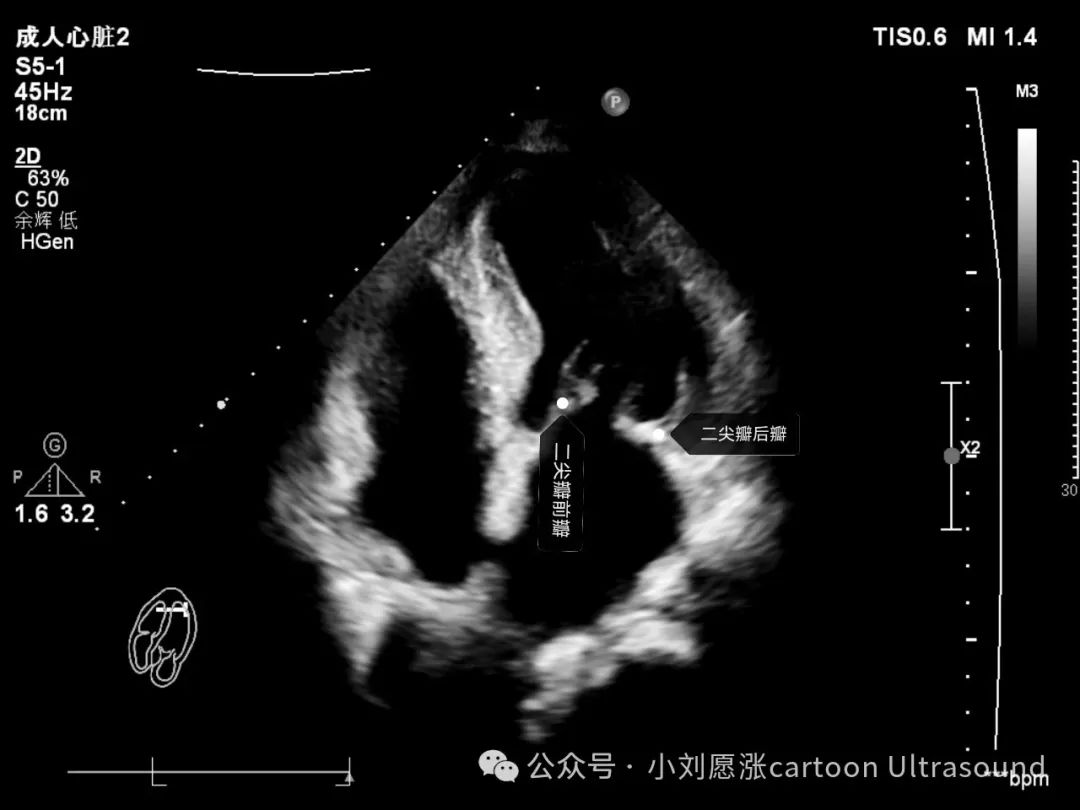

二尖瓣:2个瓣叶,分前瓣、后瓣。